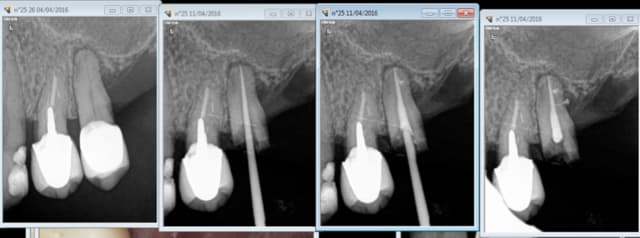

11/04/2016 à 19h57

1.Essayage du cone.

2.scellement du cone.

3. cone coupé au friendo.

4. léger down pack + foulé au machtou.

5. Chute du cone dans le canal.

6. thermo compaction au mac spadden.

Capture d e cran 2016 04 11 17.51 - Eugenol

Capture d e cran 2016 04 11 17.52 - Eugenol